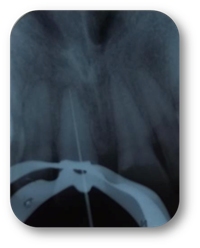

Se apreció lesión apical en la pieza 2.1 (imagen 1). Al realizar el acceso con una fresa bola de tallo largo #6 se tomó la radiografía de cavometría con la lima Flex R #20 a 20 mm (imagen 2), posteriormente se colocó pasta de hidróxido de calcio y se dejó durante un mes, después se tomó la radiografía de cronometría con cono #55. Se realizó la técnica de Crown Down para limpiar la parte coronal. Se instrumentó a partir de la lima #20 hasta la lima #55 master a 20 mm y se realizó retroceso hasta la lima #80. Al término del tratamiento se usó la técnica de condensación lateral combinada con vertical de gutapercha (imagen 3).

Imagen 1

Imagen 2

Imagen 3

Imagen 4